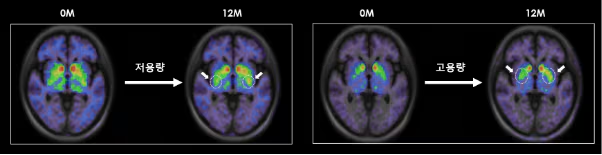

根據S.Biomedics公司本月初在奧地利維也納舉行的國際會議上公布的研究結果,低劑量和高劑量治療組患者的運動功能評分較植入前均提高了高達28.9%。低劑量和高劑量組患者的精神和情緒癥狀以及自主神經癥狀也均得到顯著改善。

尤其是在干細胞治療帕金森病植入一年后,對腦成像圖像進行分析后發現,多巴胺轉運蛋白的表達較植入前有所增加。干細胞治療的開發者、延世大學醫學院金東旭教授指出:“這表明干細胞在腦內存活,成熟為多巴胺神經細胞,并與周圍區域和突觸(神經細胞之間的連接)形成整合。”他補充道:“這可以被視為帕金森病中替換死亡多巴胺神經細胞的根本治療機制的有力證據。”